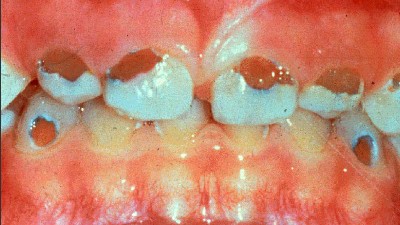

Alle fakta viser, at fluorid ikke har noget med cariesfrihed at gøre. Og cariesfrihed er det vi ønsker for risikopatienterne og alle andre. Netop for risikopatienterne er forskernes forbryderiske udtalelser gift. Når man har set små børn med masser af huller, skrigende af smerter og angst i tandlægestolen; og man ved, at fluor er medvirkende årsag, fordi det får folk til at slække på plakfjernelsen. Så undrer man sig over, at myndighederne tillader, at kvaksalvere, der burde sidde bag tremmer, går frit omkring. At kalde det videnskabelig uredelighed er århundredets underdrivelse.

Med kampagner og anbefalinger om fluor og sukker er der sat spørgsmålstegn ved tandplejens reelle hensigter. Det er kun regelmæssig plakfjernelse der kan give cariesfrihed. Alle andre metoder kan kun medføre en sænket cariesprogressionshastighed. Sålænge der er plak på tænderne vil der være caries. Uden plak er der ingen caries, helt uafhængigt af fluor og sukker. Stadig flere er cariesfrie, en cariesfrihed som helt uden tvivl er opnået ved bedre plakfjernelse. Men der er stadig risikopatienter med caries som har brug for bedre regelmæssig plakfjernelse. Den plak der er årsagen til caries på risikopatienternes tænder, har de netop på grund af den forvirring som kvaksalverne skaber omkring plakfjernelse med sukker og fluor. De har ikke skyggen af bevis for at de cariesfri bruger mindre sukker eller mere fluor. Vi burde for længst have været cariesfrie allesammen. Men sålænge kvaksalverne får lov til at udbrede deres løgne, vil der være ofre der falder for dem. Små børn vil til stadighed komme grædende til tandlægen med huller i tænderne forårsaget af plak der ikke er blevet fjernet på grund af de skadelige fluor- og sukkerkampagner.